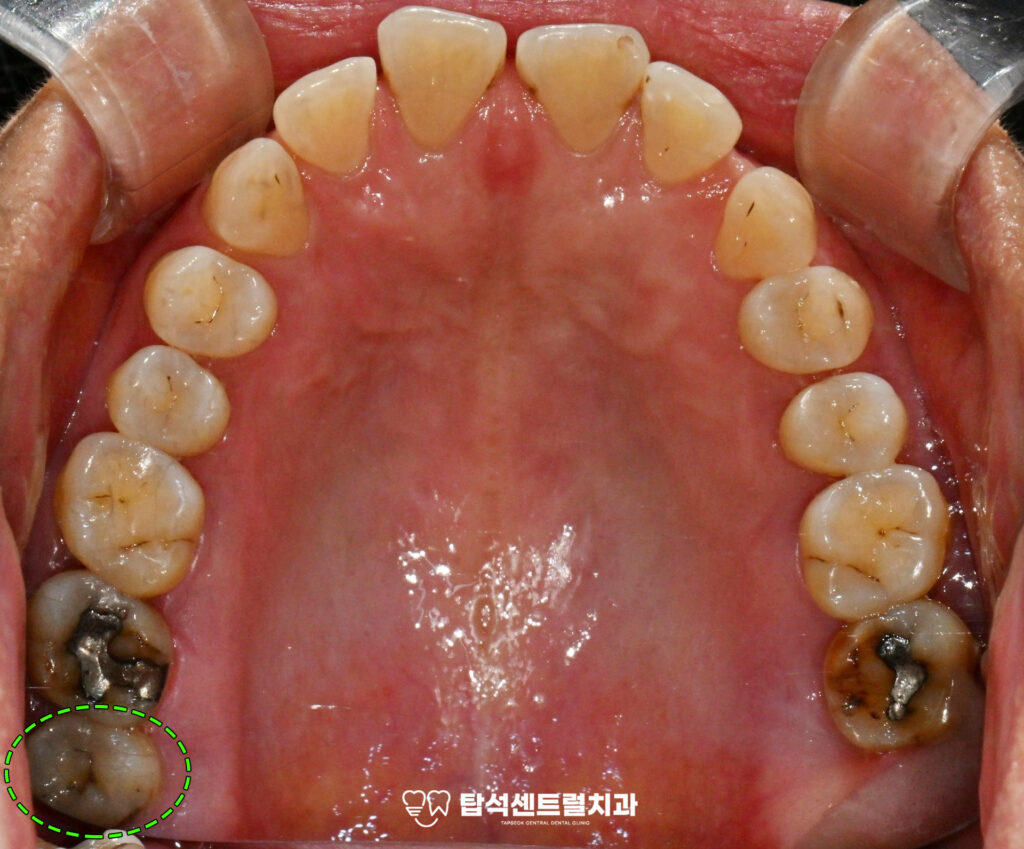

왼쪽 위 아래 어금니에서

통증이 느껴진다면 잇몸 염증을

의심해볼 필요가 있습니다.

특히 음식을 먹을 때 불편함이

지속되거나 이가 흔들리는

느낌이 든다면, 치주 질환이

꽤 오랫동안 진행되어왔을

가능성이 높습니다.

엑스레이 촬영을 통해 구강 상태를

확인하면 치주염으로 인한 전반적인

치조골 소실이 관찰되는 경우가 적지 않습니다.

다수 치아에서 나타난 치경부 마모증은

레진으로 수복하는 것이 적절합니다.

치경부 마모증은 치아 목 부분이 닳아서

움푹 파인 상태를 말하며,잘못된 칫솔질이나

이갈이 습관으로 발생합니다.